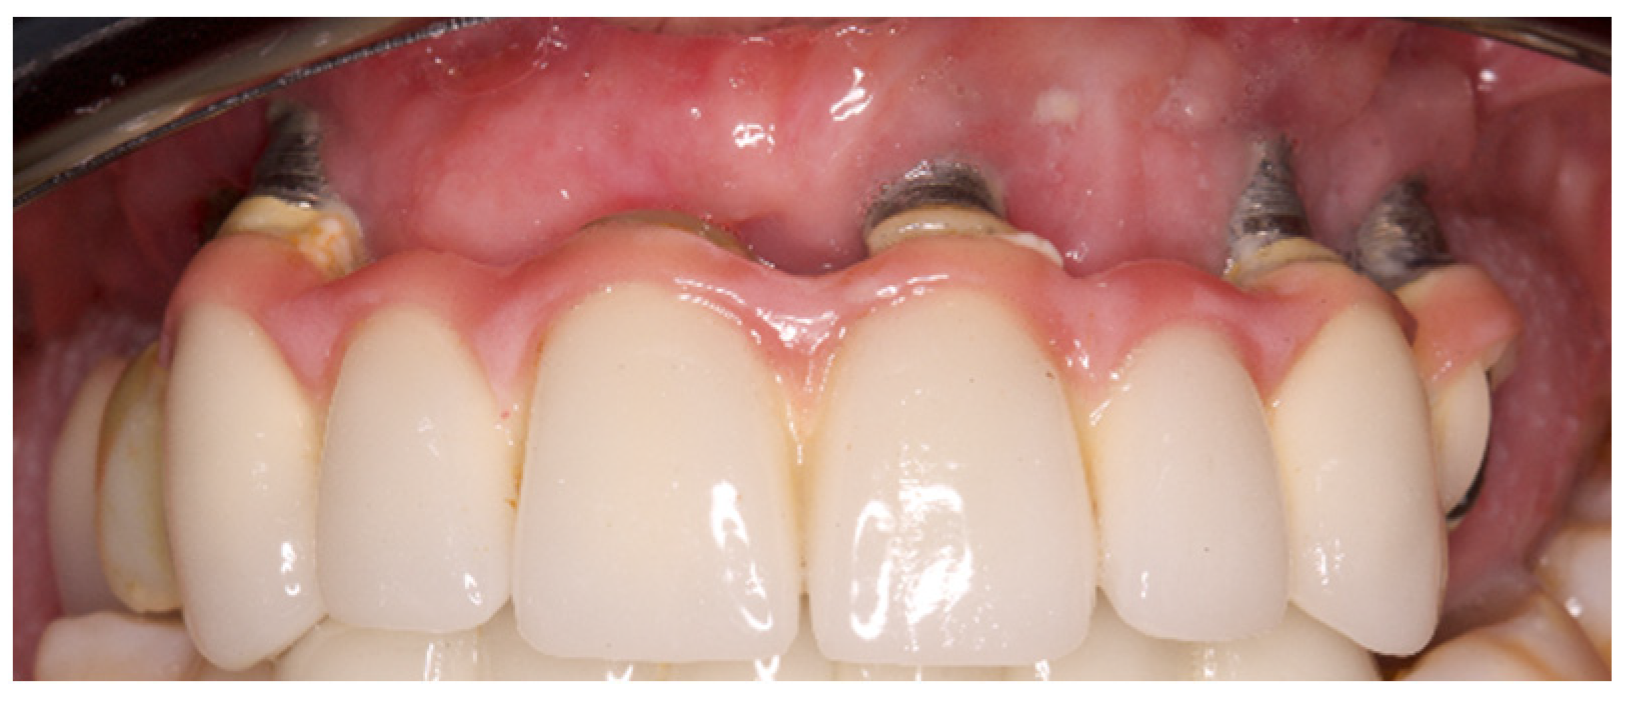

:1. Introduction

2. Method and Materials

2.2. Setting and Participants